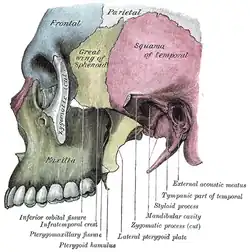

Esquerda fossa infratemporal.

Esquerda fossa infratemporal. -